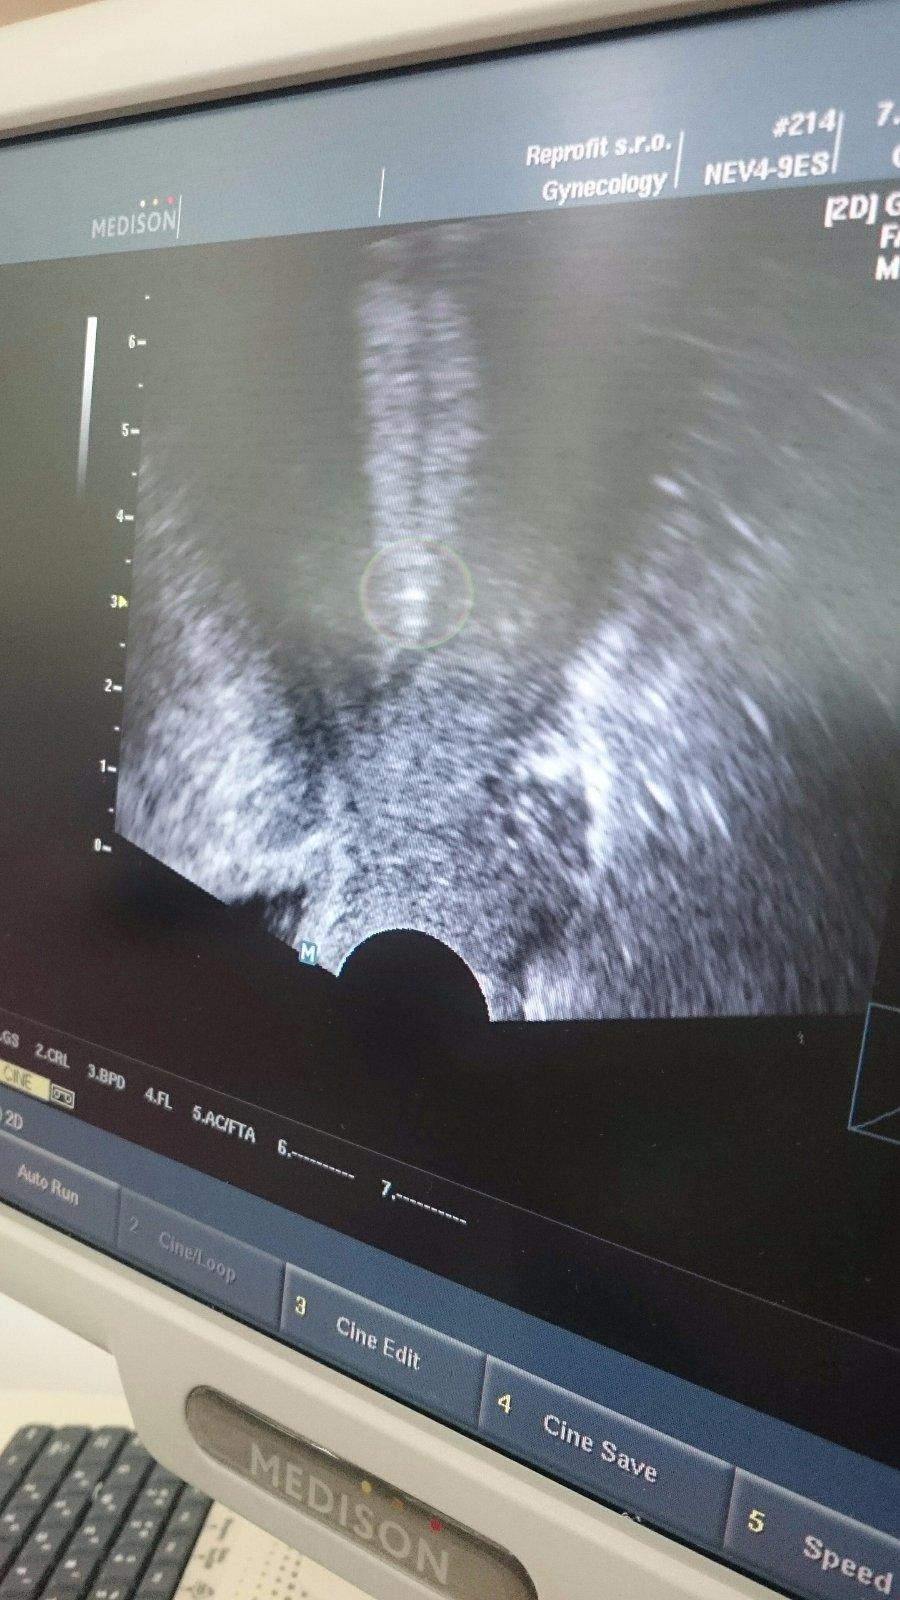

Ahojte baby, tak som po vklade. Vrana trošku "donútil" môjho muža ísť tiež dnu,tak tentoraz mam aj fotky 🙂)

1. Foto 1Xb/1, Vrana bol spokojný,že super kvalita,že sa rozmrazila tak,že ani by nepovedal,že bola zamrazena.

2.foto Agatka v "domčeku". Tak už nech tam len zostane.